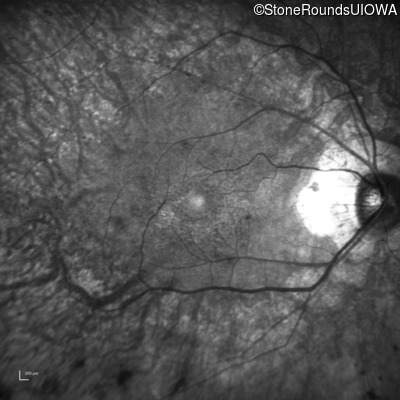

The clinical features supporting the diagnosis of MAK-associated autosomal recessive retinitis pigmentosa in this patient include: night blindness and constricted visual fields (with temporal predilection) as his earliest symptoms; bone-spicule-like pigmentation (with nasal predilection) and narrowed arterioles on fundus examination; loss of outer retinal structures on OCT; a similarly affected sibling; Jewish ethnicity; and, normally sighted parents.

Age at visit: 55 years